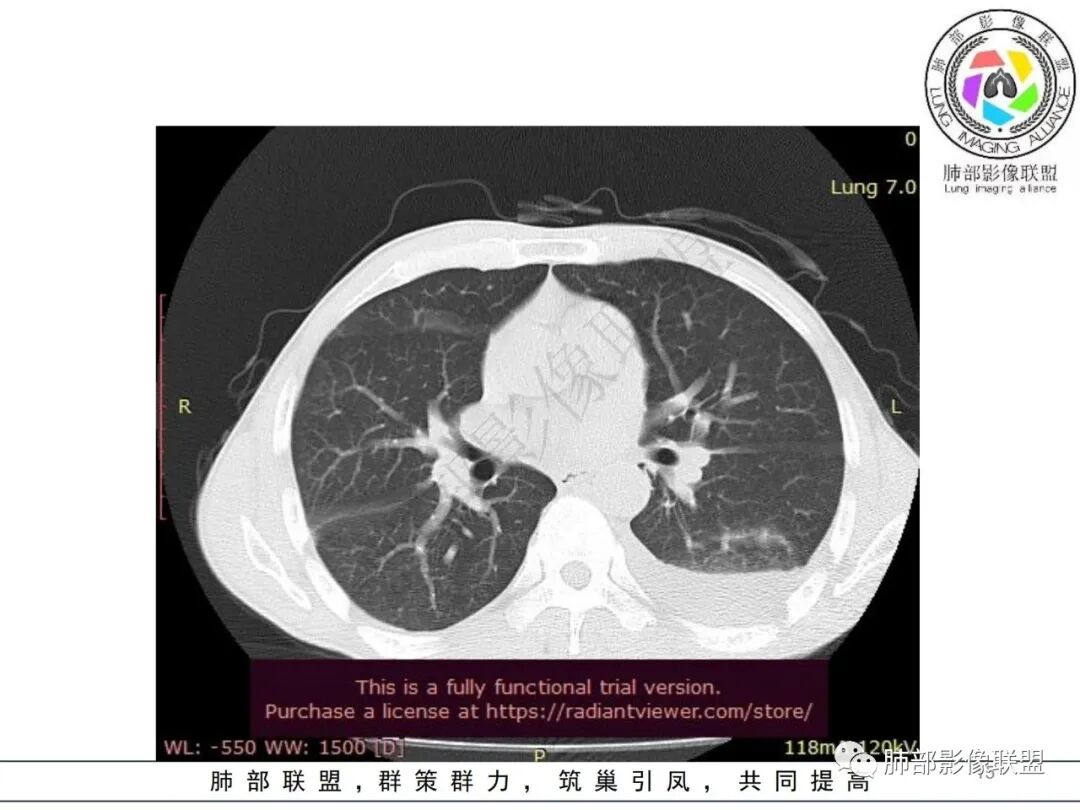

两肺多发斑片状实变影,周围GGO

主体还是沿支气管,大片叶段性分布

影像上急性感染,大叶性病变为主

我纠结的是,这是气道来源还是血播,如果血播加上海南下田,优先类鼻疽,如果气道,军团也要考虑,只是没见过军团反晕,除非免疫缺陷,混合感染。另外肺克,肺克好像气血皆可,后面反晕出洞,如果没有海南,也要考虑吧,肺克也是免疫妥协相关菌

早上这里是支持血播的

这些层面又像气道

这一类表现等于是病灶没有沿气道趋势,不支持以肺实质、支气管的分布区域,我认为是沿气道到播散,间质蔓延为主

这是比较早的病灶,其他的比较晚的病灶

觉得后面那些符合血道,左下的更符合气道的

影像表现:双肺多发结节、实变影,大部分病灶边界不清,随机分布趋势,左下肺“反晕征”,似有形成空洞趋势。左侧胸腔积液。治疗后复查 ,大部分病灶吸收好转,呈较为典型血播分布,肝脏低密度块影,边界不清,符合肝脓肿。